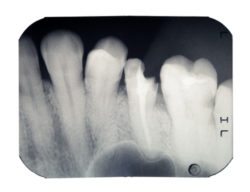

We believe that every aspect of dentistry can be cosmetic. For example, when we perform restorative procedures, we strive to ensure these repairs look natural and blend with the patient’s smile. When we rebuild damaged teeth, we employ techniques and restorations using lifelike materials and digital impressions, creating custom crowns and veneers. In today’s quiz, we’re taking a look at exactly how we rebuild damaged teeth.

- True. Hen a tooth is damaged, then the protective outer layer of enamel can become compromised. As a result, harmful bacteria can then reach the more sensitive layers of inner tooth structure, allowing decay and eventually infection to occur. When you damage a tooth, even if the chip seems minimal, you should still see your dentist right away.